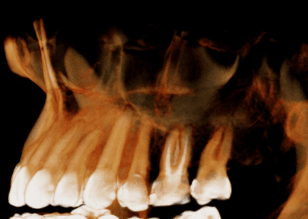

左上第一小臼齒蛀牙缺損 齒質蛀牙嚴重導致斷裂,骨頭破壞需植入牙根時補骨促進骨整合 待3個月後骨整合完